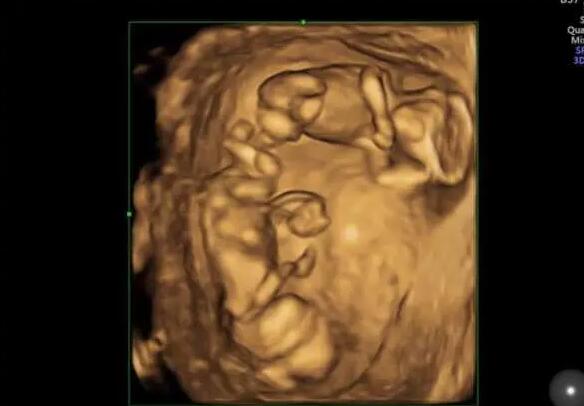

醫院簡介:目前專業技術人員18人,其中生殖臨床醫師6人(包括1名男科臨床醫師),實驗室人員5人,護理人員7人。碩士研究生9人。中心由生殖醫學臨床(包括男科),生殖醫學實驗室,生殖醫學病房三部分組成。生殖醫學科是嚴格按照衛生部[2003]176號文件和省衛生廳的規劃要求組建的。成立了院生殖醫學倫理委員會,在倫理委員會的監督和指導下開展工作。

022臨沂市人民醫院做試管嬰兒取卵只有2個能成功嗎?

試管嬰兒的成功率并不取決于卵泡的數量,而是取決于卵泡的質量。因此,卵泡數量少不要太擔心,臨沂市人民醫院做試管嬰兒的成功率是相對較高的,臨沂市人民醫院做試管嬰兒的成功率具體如下:

1.臨沂市人民醫院生殖科每年有近10萬名不孕不育癥患者接受治療,完成新鮮、解凍周期超過10000個,總成功率約為53%-55%。在該醫院做試管嬰兒取卵只有兩個卵子,如果兩個卵泡的質量較好,即使只有兩個卵泡,成功率也相對較高,可以達到50%左右;

2.但是如果卵泡質量不好,成功率會稍微低一些,可能只有30%-40%;

以上就是“2022臨沂市人民醫院試管嬰兒成功率一覽,取卵只有2個能成功嗎?”的全部內容了,事實上,做試管嬰兒并不是卵泡越多越好,即使卵泡的數量再多,質量不好,也是徒勞的。